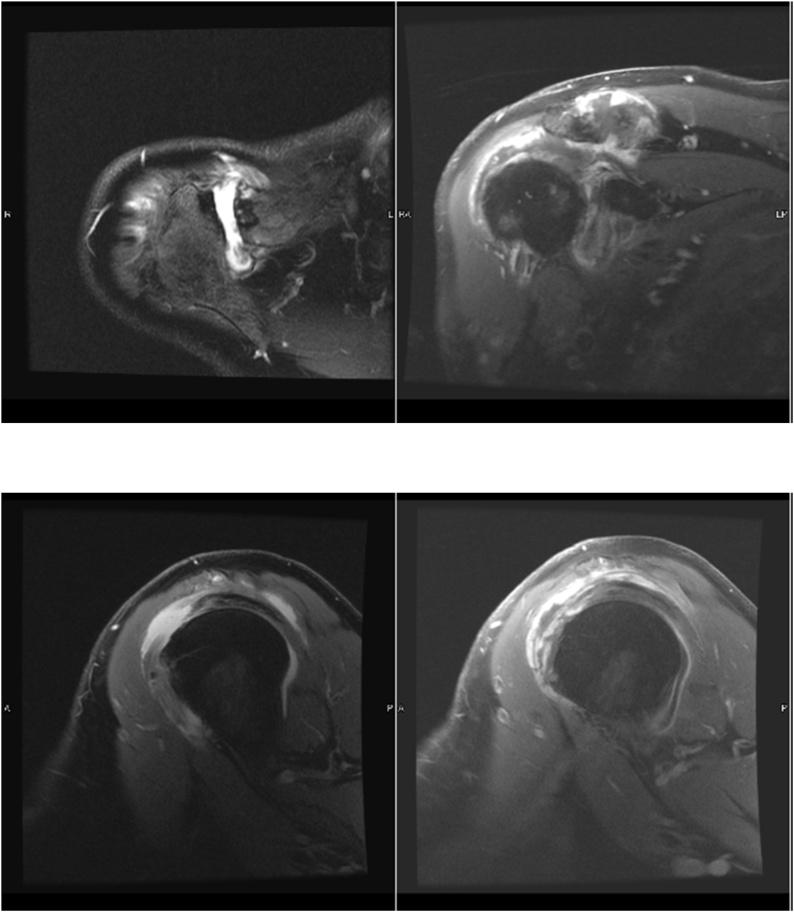

Bilateral joint septic arthritis is relatively rare. We present an uncommon case of atraumatic bilateral septic shoulders in an elderly man with a history of heart disease and insidious bilateral shoulder pain after golfing 18 holes. This presentation is unique not only in its rarity but also in its impact on our understanding of septic arthritis in the setting of medical comorbidities and a relatively unimpressive presentation. With a recent golfing day just prior to presentation, differential diagnoses other than septic arthritis included deltoid/rotator cuff muscle strain, acute on chronic rotator cuff tendinosis, acute on chronic rotator cuff tearing, acute flare up of osteoarthritis, rheumatoid arthritis, or crystalline arthropathy. With elevated inflammatory markers and an equivocal physical examination, our patient underwent advanced imaging via MRI and subsequent bilateral glenohumeral joint diagnostic aspirations that were consistent with septic arthritis due to his complaining of contralateral shoulder pain shortly after his admission. Immediately after said diagnosis was made, the patient was taken back for emergent bilateral open irrigation and debridement, as septic arthritis is an orthopedic emergency, and went on to recover appropriately on culture-directed intravenous antibiotic therapy.

病例介绍

双侧关节化脓性关节炎相对罕见。我们报告一例不常见的病例,一名患有心脏病的老年男性出现非创伤性双侧化脓性肩关节,在打了18洞高尔夫球后出现隐匿性双侧肩部疼痛。这种表现不仅因其罕见而独特,还因其对我们理解合并内科疾病情况下的化脓性关节炎以及相对不明显的表现有影响。在发病前最近有打高尔夫球的经历,除化脓性关节炎外的鉴别诊断包括三角肌/肩袖肌拉伤、慢性肩袖肌腱病急性发作、慢性肩袖撕裂急性发作、骨关节炎急性发作、类风湿关节炎或结晶性关节病。由于炎症指标升高且体格检查结果不明确,我们的患者接受了磁共振成像(MRI)高级影像学检查,随后进行了双侧盂肱关节诊断性穿刺,穿刺结果与化脓性关节炎相符,因为患者入院后不久就抱怨对侧肩部疼痛。在做出上述诊断后,患者立即被送回进行紧急双侧开放性冲洗和清创,因为化脓性关节炎是骨科急症,患者在接受针对培养结果的静脉抗生素治疗后顺利康复。